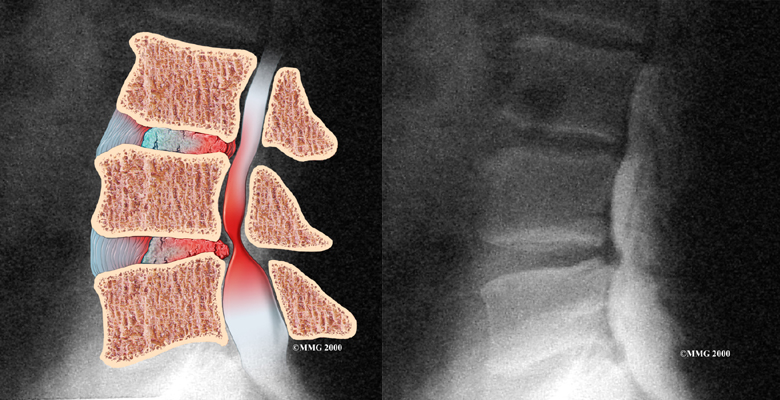

Рентген шейных позвонков при спина бифида

Раздел: Фотозарисовки